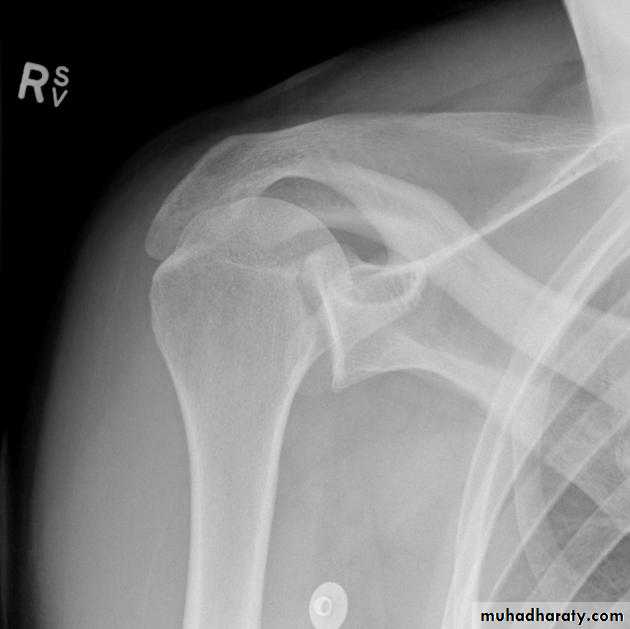

-Anterior shoulder dislocation:

*most common type about 96% of total shoulder dislocation.

*40% recurrent.

* 15% fracture greater tuberosity.